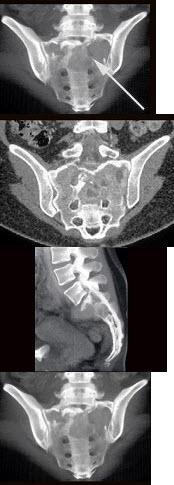

正常尾椎骨ct图,女性尾椎骨图片

正常骶尾骨x线图片

正常骶尾骨ct图片

骶尾骨骨折ct图片

骶尾椎ct解剖图

骶尾骨ct图片

骶尾椎正常侧位图解

骶椎ct解剖图